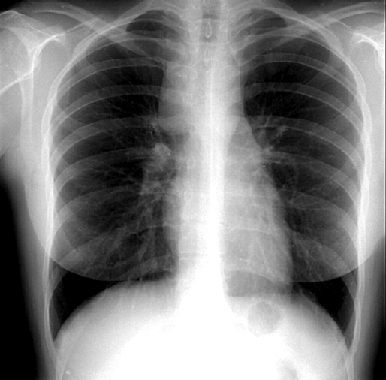

У 90% первичных больных отмечается поражение лимфатических узлов выше диафрагмы. Первичная локализация только ниже диафрагмы встречается лишь у 10% больных. Кольцо Вальдейера, околоушные, затылочные и локтевые лимфатические узлы поражаются крайне редко и всегда требуют уточнения диагноза для исключения других вариантов лимфом. Изолированное увеличение внутригрудных лимфатических узлов отмечается у 15% больных и нередко длительно существует бессимптомно (рис. 4).

Рисунок 4. Лимфома Ходжкина. Рентгенограмма грудной клетки в прямой проекции

Увеличение лимфатических узлов средостения

При значительном увеличении медиастинальных лимфатических узлов иногда возникает сухой кашель. Однако боли в грудной клетке и синдром сдавления верхней полой вены возникают только при очень большом увеличении лимфатических узлов средостения. При больших конгломератах лимфатических узлов в средостении возможно прорастание опухоли в плевру, легочную ткань, перикард, трахею и бронхи, пищевод, грудину и мягкие ткани передней грудной стенки. Нередко возникает плеврит (как правило — транссудат) и реже — перикардит. Диагностические клетки Березовского — Рид — Штернберга при микроскопии осадка плевральной жидкости обнаруживаются редко. У части больных с массивными медиастинальными лимфатическими узлами, при сдавлении ими верхней полой вены, плеврит или перикардит (всегда транссудат) могут развиваться при отсутствии опухолевого поражения плевры или перикарда. Кроме того, при массивном поражении лимфатических узлов средостения почти всегда отмечается умеренное увеличение печени, что не является признаком ее метастатического поражения, а вызвано сдавлением верхней полой вены.

5) обязательным для всех больных является ;рентгенография ;грудной клетки. Для полноценной диагностики поражения лимфатических узлов средостения рентгеновские снимки должны быть выполнены в прямой и боковой проекциях. Это исследование позволяет уточнить состояние лимфатических узлов средостения, легочной ткани и плевры. ;При отсутствии изменений на рентгенограммах обязательна КТ грудной клетки, которая позволяет выявить невидимые на стандартных рентгеновских снимках медиастинальные лимфатические узлы. КТ грудной клетки также необходима и при массивном поражении лимфатических узлов средостения, т.к. позволяет обнаружить мелкие очаги в легочной ткани и прорастание в мягкие ткани грудной стенки, грудину, плевру и перикард. Флюорография не дает полноценной картины изменений лимфатических узлов средостения и легочной ткани и не может считаться современным адекватным методом диагностики у больных лимфомой Ходжкина;